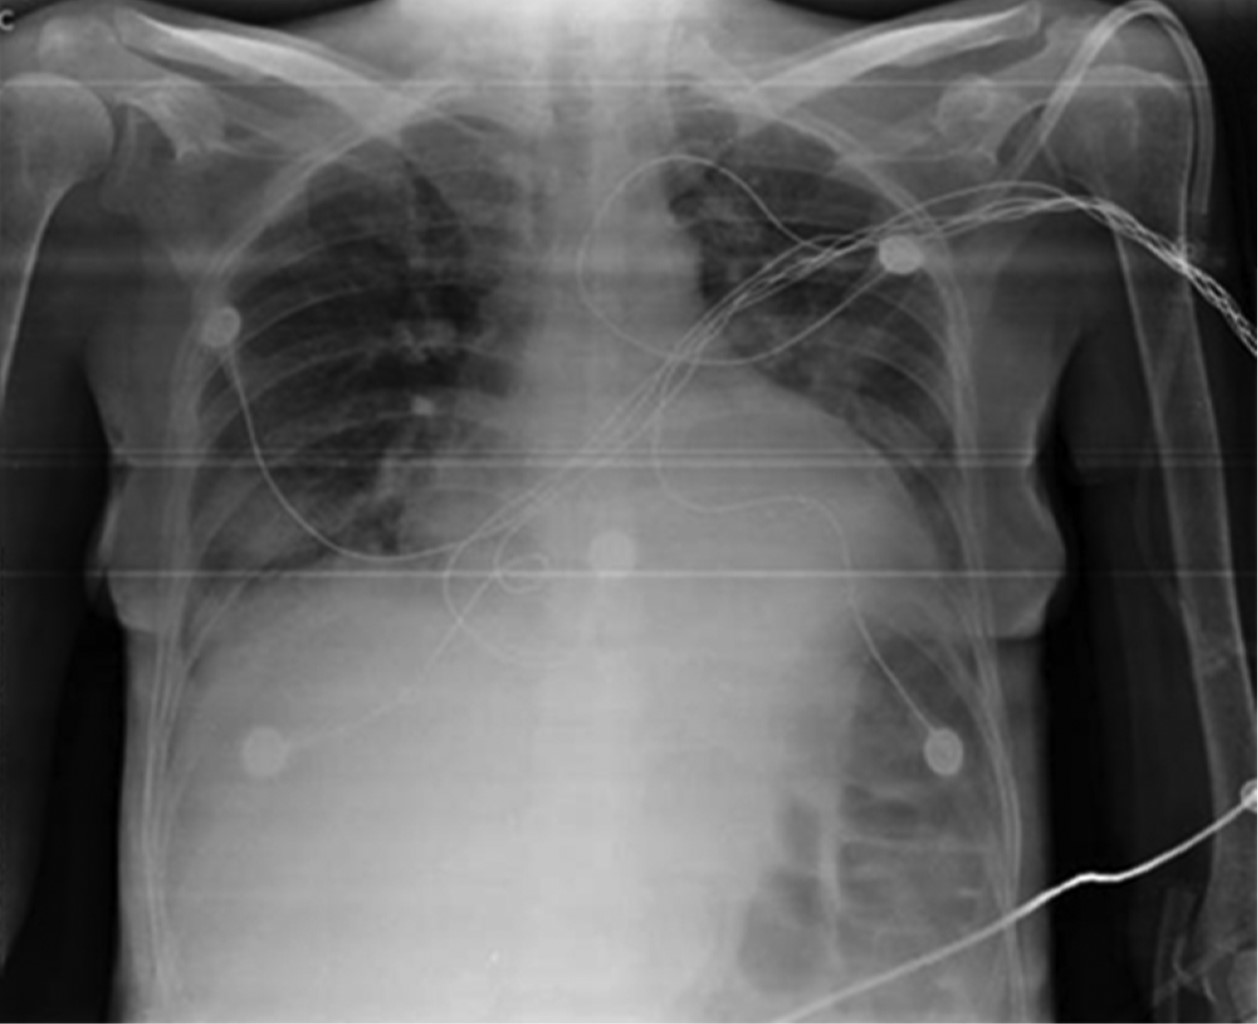

Mujer de 40 años de edad postnefrectomía secundario a absceso perirrenal, deterioro hemodinámico y respiratorio que requirió manejo en la Unidad de Cuidados Intensivos (UCI). La paciente presentó ventilación prolongada con necesidad de traqueotomía. Después de 38 días de estancia en la UCI se logra la decanulación de traqueostomía con éxito. Sin embargo, al cuarto día posterior a la decanulación presenta atelectasia completa del pulmón izquierdo sin datos de inestabilidad respiratoria (Figura 1). Las atelectasias completas se caracterizan radiológicamente por pérdida de la aireación pulmonar, radiopacidad de la región afectada, pérdida de la silueta cardiaca, ascenso de la cúpula diafragmática, desplazamiento de las estructuras mediastinales y tráquea de forma ipsilateral. Debido a las características del caso y las posibles complicaciones de manejo por medio de broncoscopia, se decide abordar de forma conservadora por medio de técnicas de fisioterapia pulmonar. Dentro del manejo fisioterapéutico se utilizaron técnicas de expansión torácica con apoyo de presión positiva con bolsa válvula mascarilla + válvula de presión positiva al final de la espiración (PEEP) de 10 cmH2O, tos asistida manual, fisioterapia de tórax para el manejo de secreciones y decúbito inspiratorio controlado (EDIC). Esta última técnica prioriza la ventilación hemipulmonar colocando en supralateral el pulmón a ventilar seguido de inspiraciones guiadas y finalizadas con espiraciones asistidas por compresión manual del tórax. Después de la radiografía de control a las seis horas (Figura 2) se decide la utilización de ventilación mecánica no invasiva durante la noche como manejo coadyuvante con una presión soporte 5 cmH2O y una PEEP de 5 cmH2O. Se logra el egreso hospitalario a los ocho días del evento con seguimiento médico y fisioterapéutico (Figura 3).

Figura 1